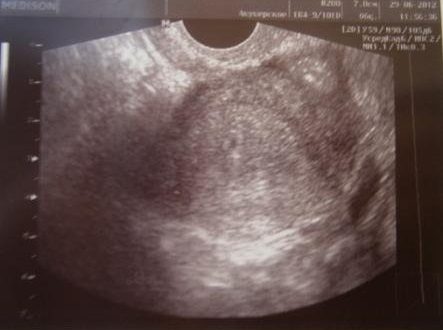

Узи и токсоплазмоз

Токсоплазмоз, диагностика, лечение и профилактика 3 Мар 2016 Беременность является особенным периодом в жизни женщины. Любое заболевание, перенесенное беременной, может пагубно сказаться на развитии плода, поэтому в этот…